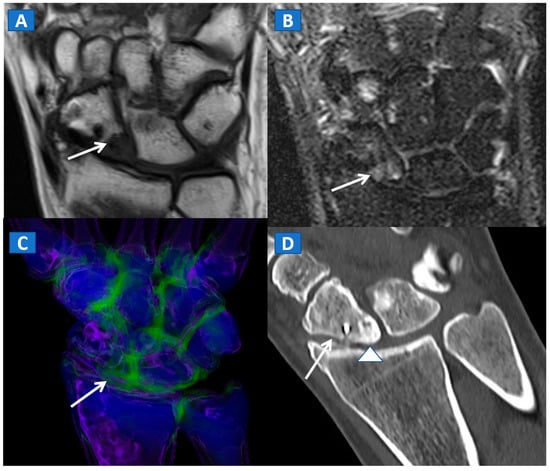

Figure 9.

A 45-year-old male with persistent pain after surgical fixation of a middle-third carpal scaphoid fracture. On the coronal T1-weighted (A) and STIR (B) MRI images, metal-induced and motion artifacts impede the correct evaluation of the healing process. Furthermore, subtle BME is depicted proximally (arrow). On the 3D DECT image (C), some proximal BME can be confirmed (arrow). On the 1 mm reconstructed standard CT image on the coronal plane (D), the BME appears as an area of increased density (arrowhead). There are no signs of any residual fractures adjacent to the inserted metallic hardware.